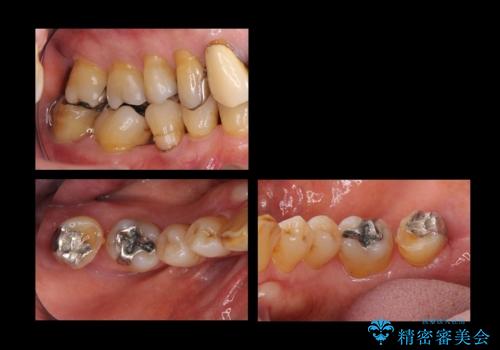

臼歯部メタルフリー再補綴